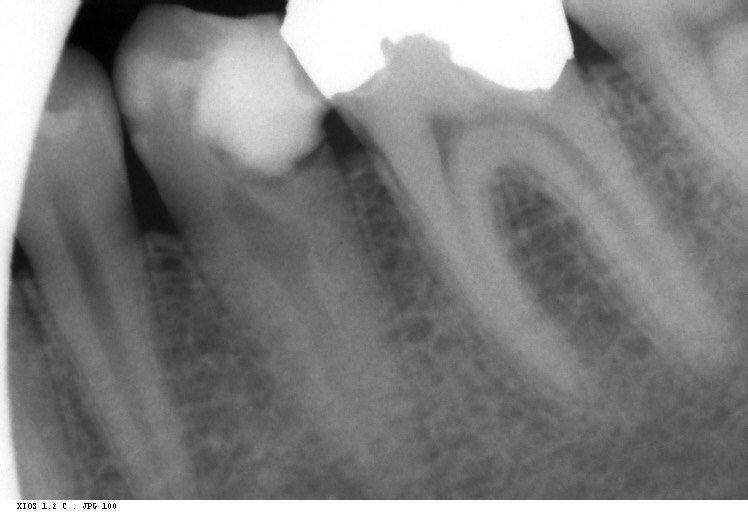

Question 21: What option is can be selected for distal tooth # 4.6?

Question 22: Which surface shows defective restoration?

Question 23: Which surface shows overhang?

Question 24: Which surface shows defective restoration?

Question 25: Which surface shows open margin?

Question 26: What option cannot be selected for mesial tooth surface # 2.8?

Question 27: What options cannot be seen in this X ray?

Question 28: What is the best option that describe distal surface of tooth # 3.5?

Question 29: What options cannot be seen in this X ray?

Question 30: What options can be selected for the tooth # 4.2?